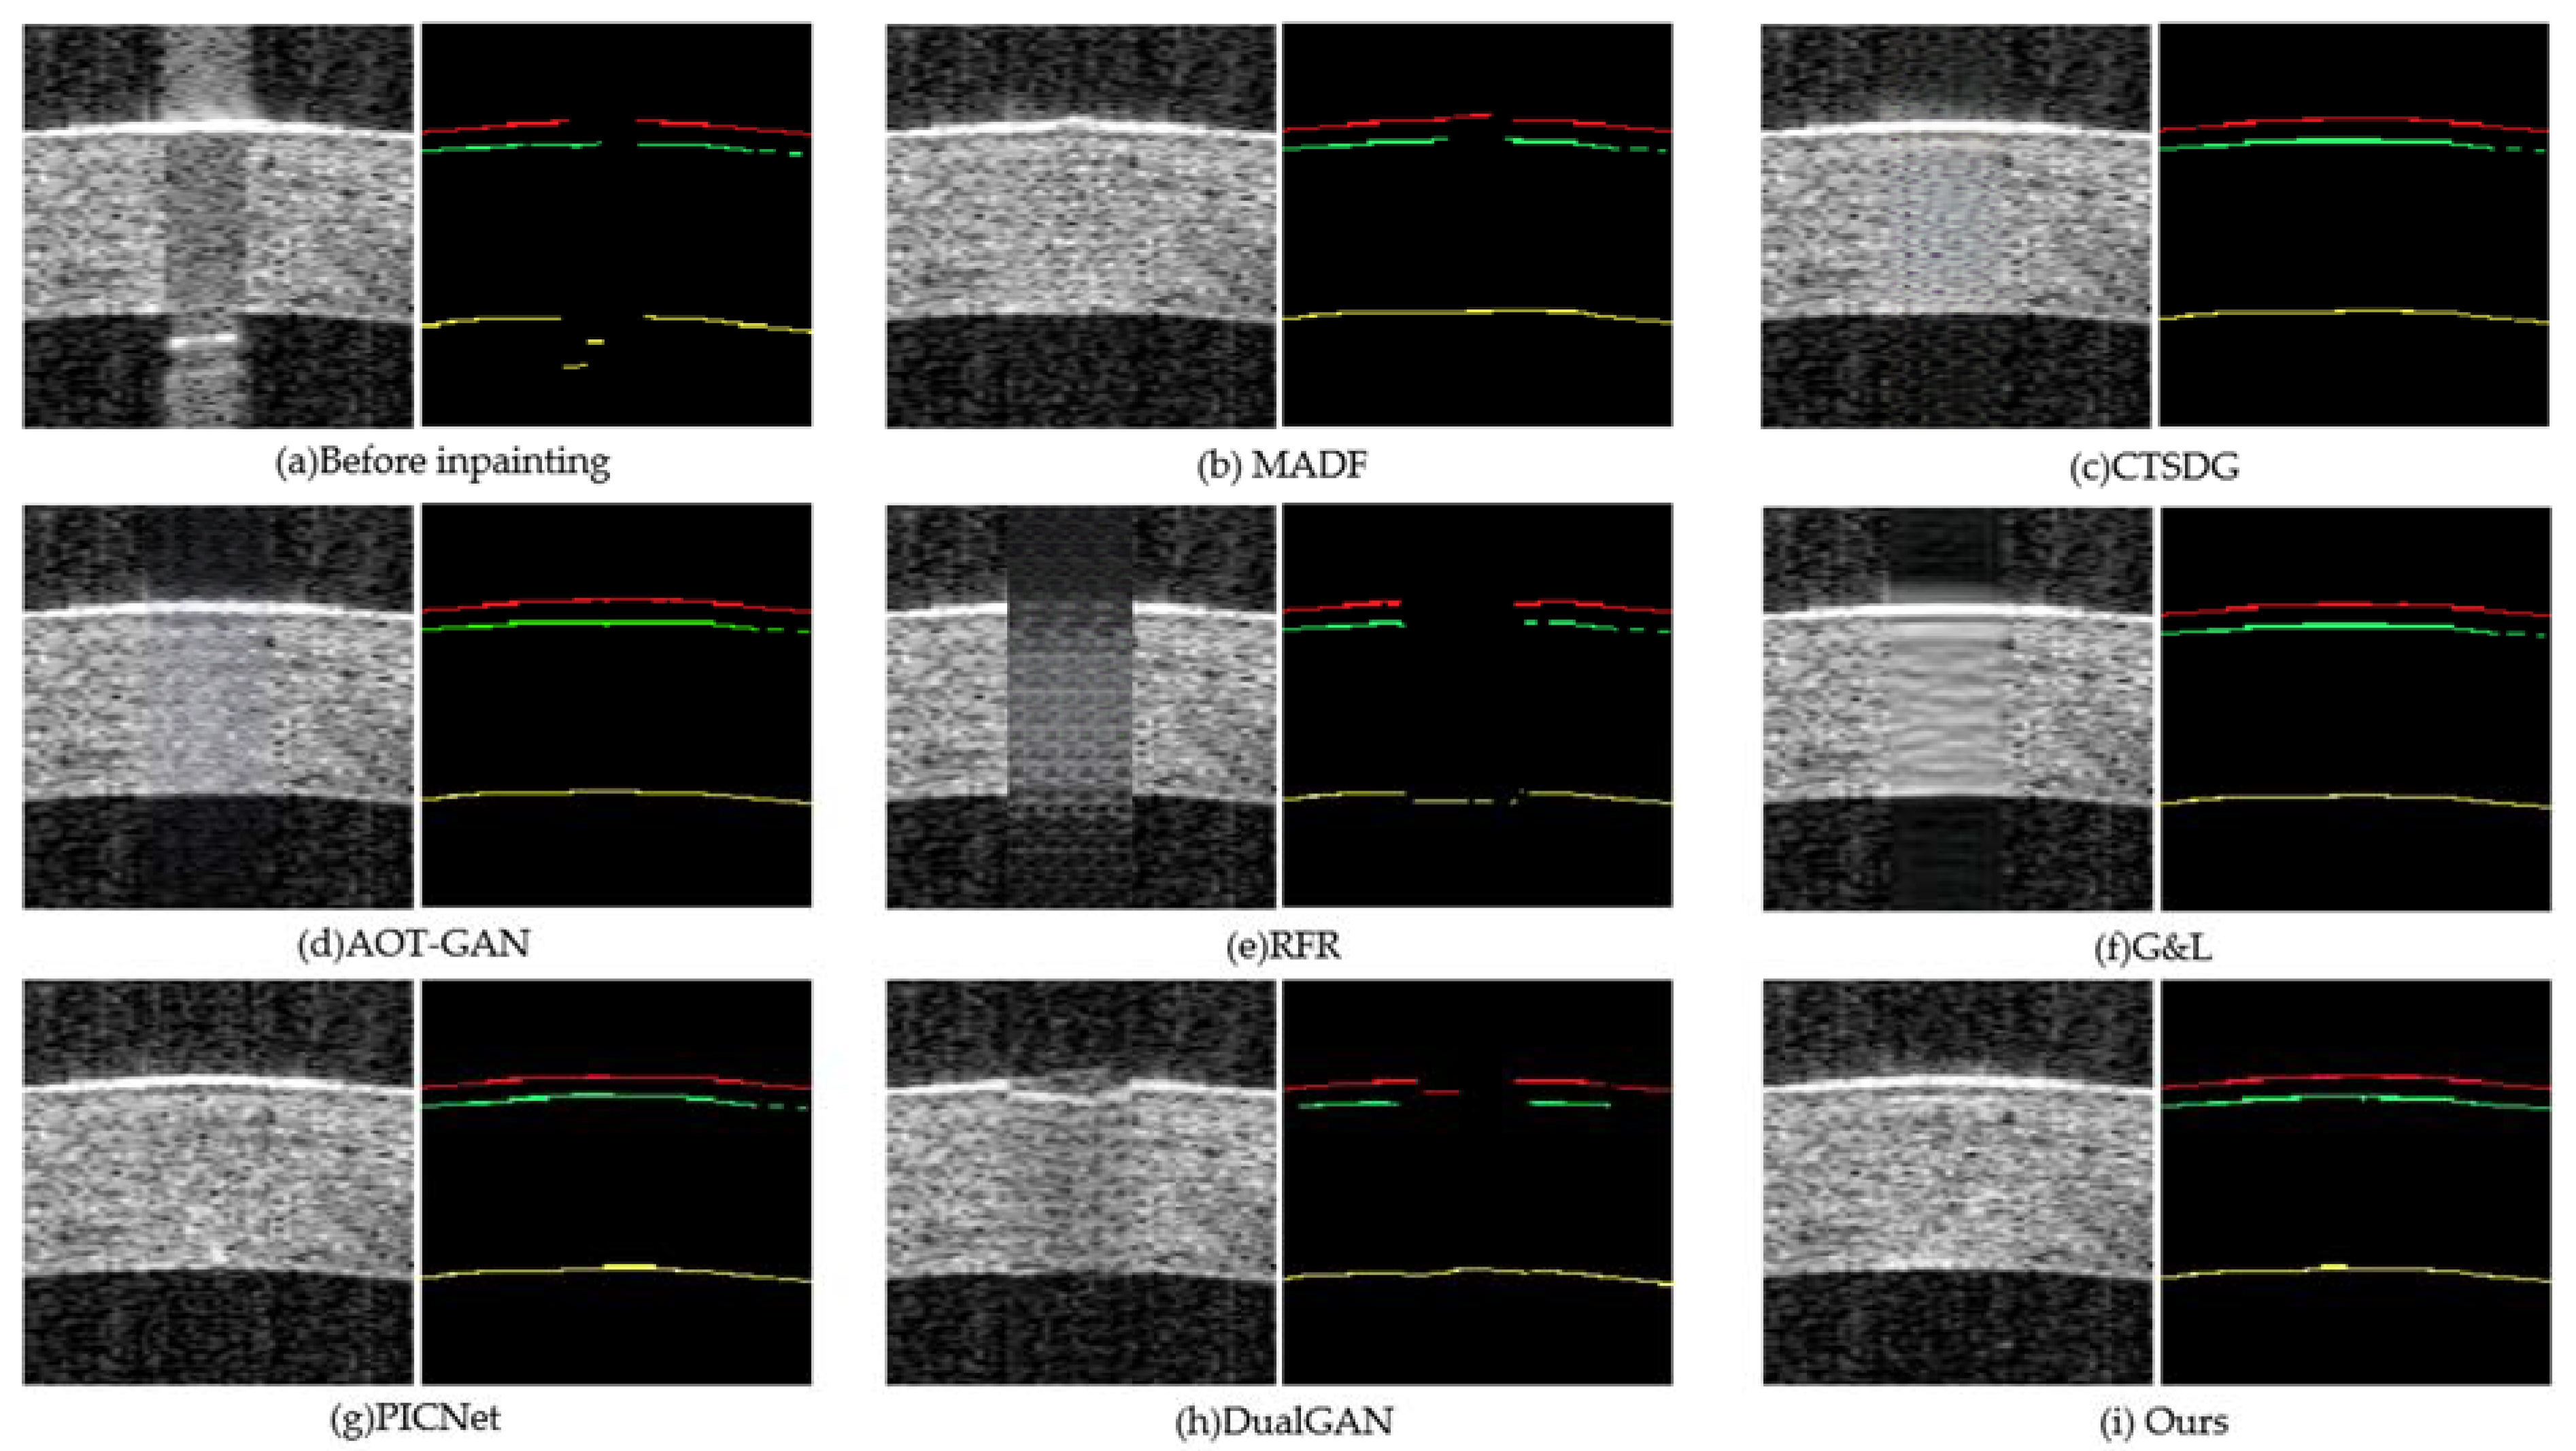

- The repair effects of different methods on corneal tissue images with different tilt degrees under the same mask conditions are shown in Figure 7;

- The results of adding different masks into the corneal tissue images with different degrees of inclination using different methods are shown in Figure 9.